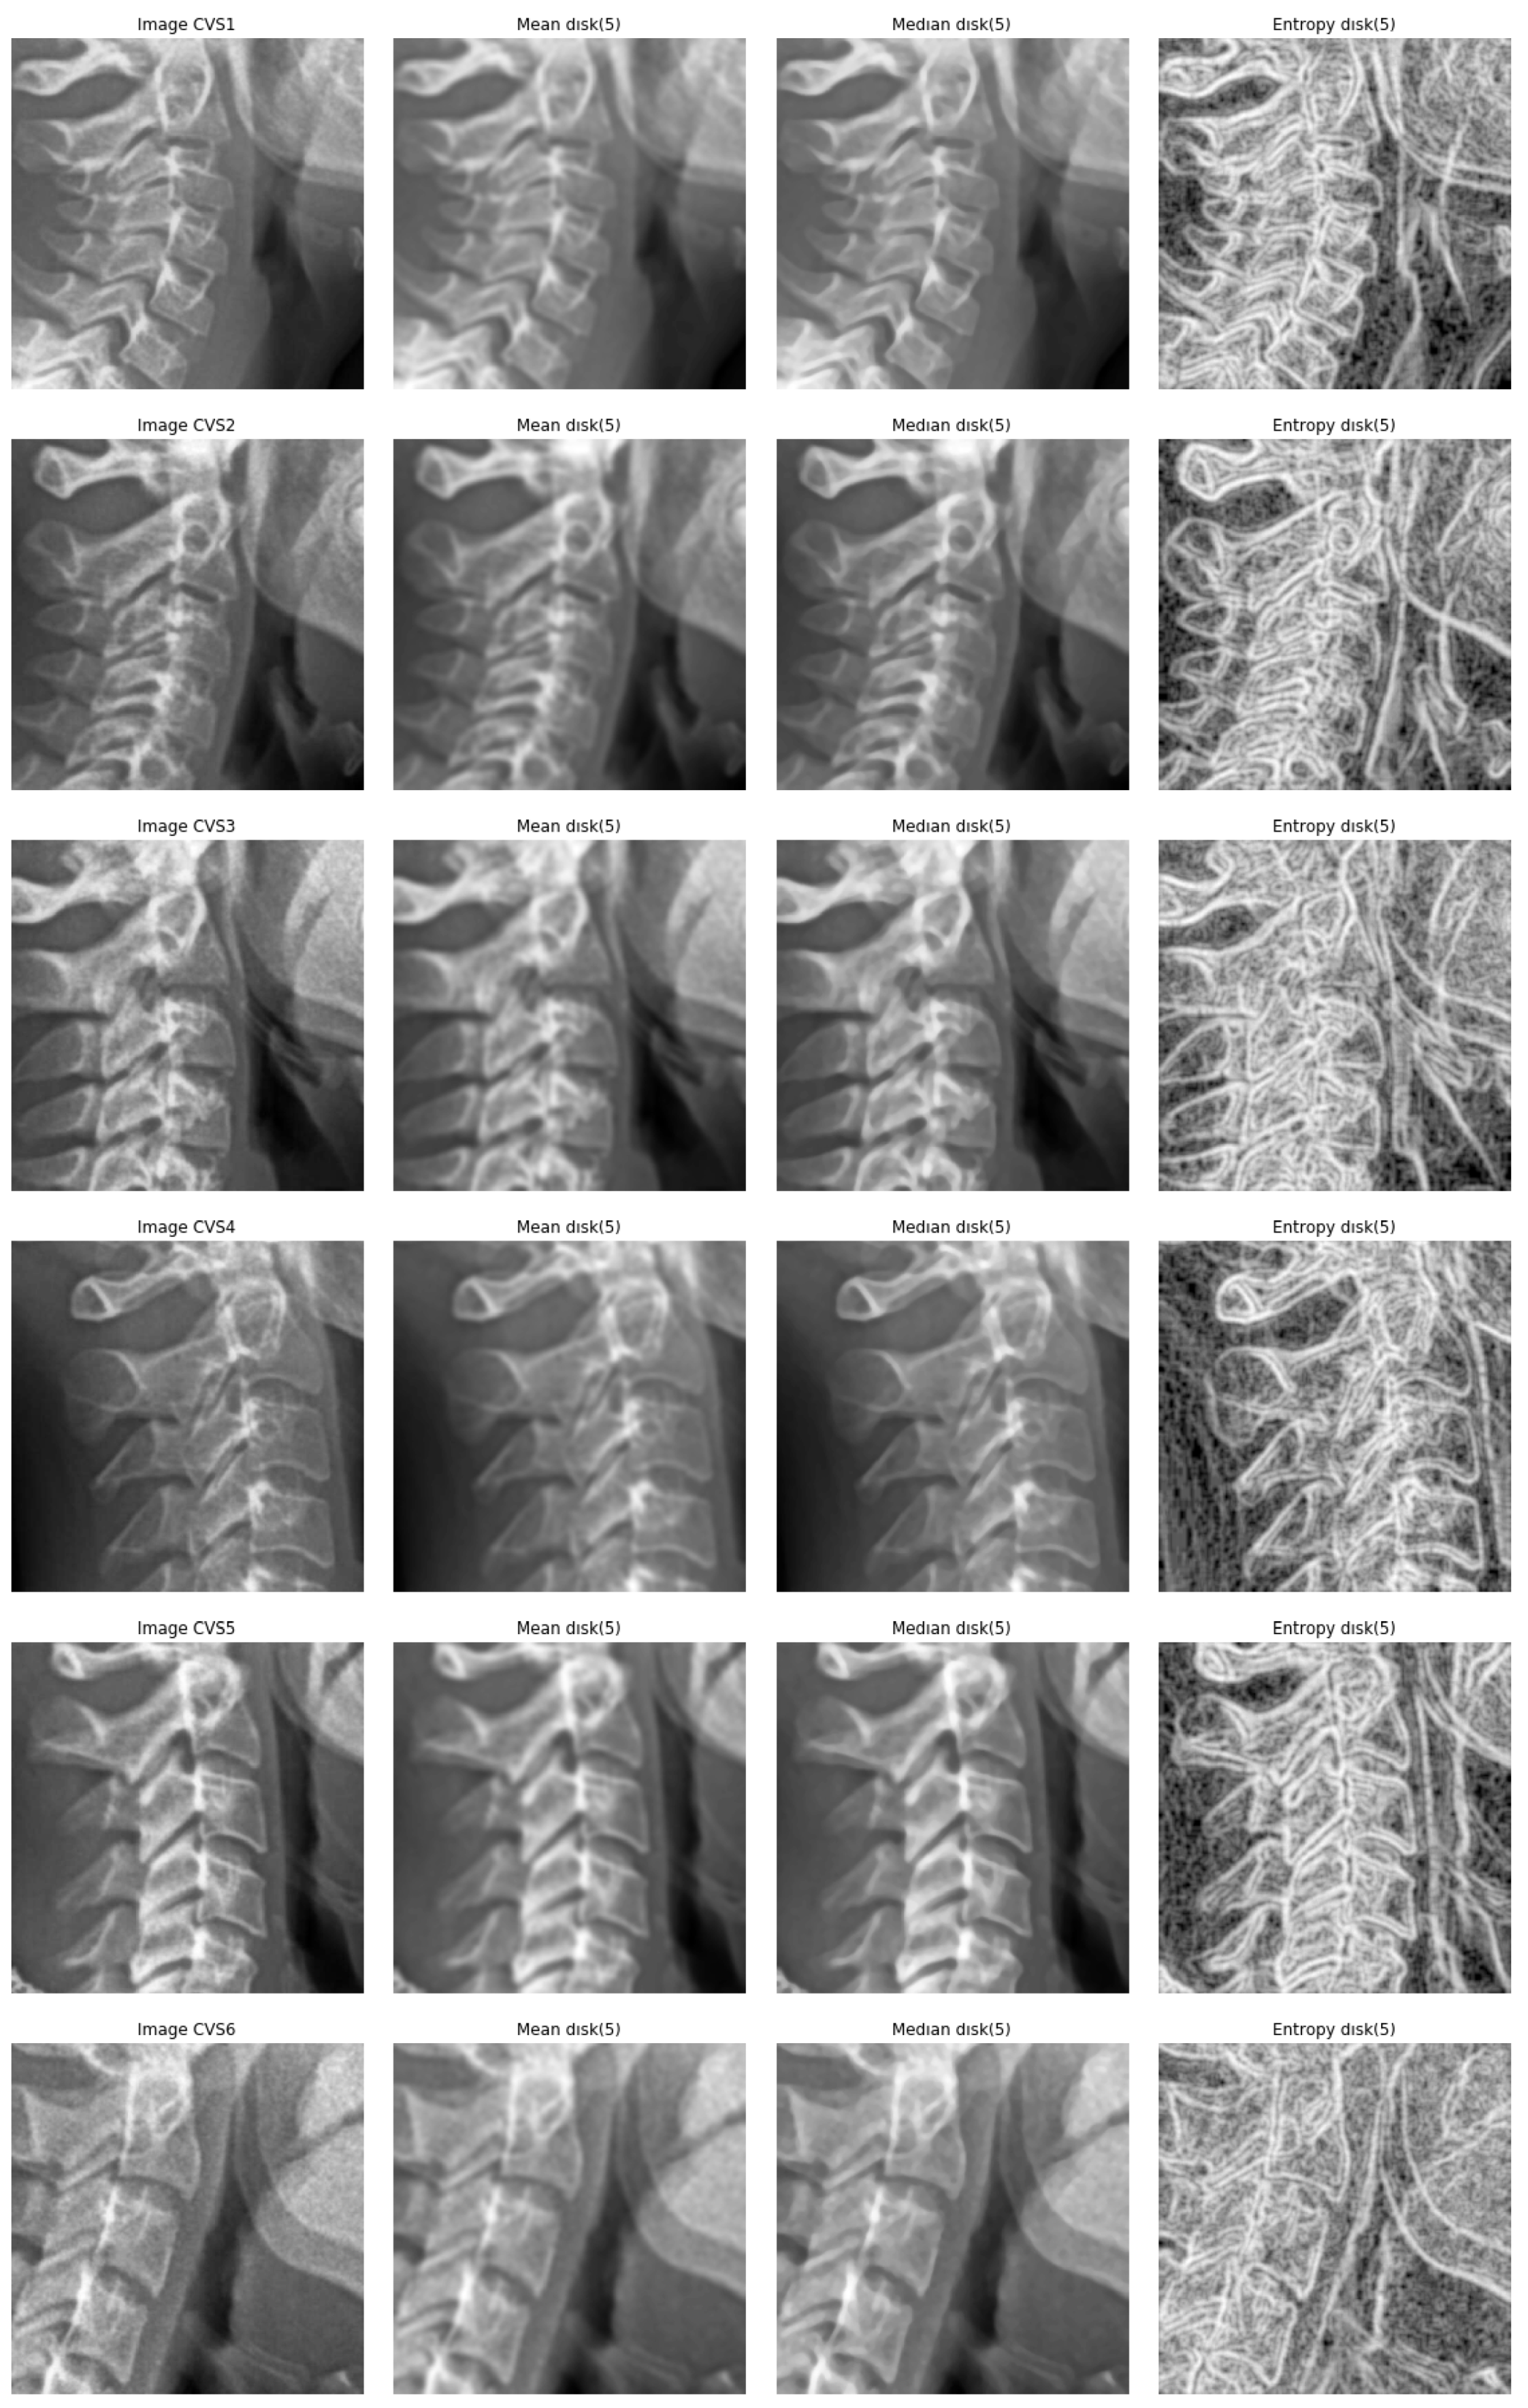

- A cropping of images of the size 512 × 512 to the specific informative part of cervical vertebra and possibly resizing them to 256 × 256 for reducing the computational costs are enough. However, to improve more, we tried different pre-processing of the images: mean, median and entropic filter to the images.

5.1. Entropic Filtering

- We did many experiments on the importance of the pre-processing of the images. Some pre-processings such as cropping on the interesting part of the image is almost always necessary, but other linear processing methods such as mean filtering or resizing did not have great impact. However, we discovered that an entropic filtering has improved the classification task.